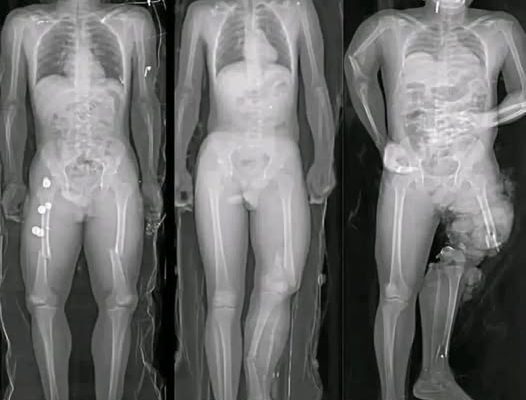

Medical research has identified a small number of myocarditis cases—an inflammation of the heart muscle—following certain mRNA vaccines, particularly among adolescent and young adult males. However, context is critical. These cases are rare, typically mild, and most individuals recover fully with minimal treatment.

Multiple peer-reviewed studies show that the risk of myocarditis from COVID infection itself is significantly higher than the risk associated with vaccination. COVID-19 as a disease has been linked to more severe cardiac complications, including inflammation, blood clots, and long-term heart damage.

In other words, when comparing risks, vaccination reduces overall heart-related danger rather than increasing it.